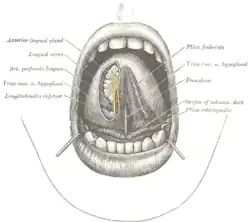

The mouth cavity. The apex of the tongue is turned upward, and on the right side a superficial dissection of its undersurface has been made. (Frenulum labeled at center right.) | |